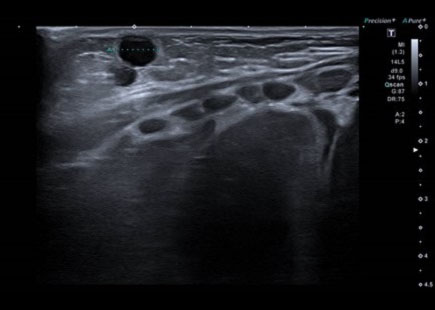

Para realizar el diagnóstico diferencial entre estas entidades clínicas, la ecografía resulta de gran utilidad. El tejido mamario en la intumescencia mamaria neonatal es relativamente hipoecoico, mientras que el aumento en la ecogenicidad es característica de la mastitis. El absceso por su parte será anecoico o ecoico dependiendo de la naturaleza de su contenido. Estos dos últimos presentarán un aumento del flujo en el tejido graso periférico en el Doppler color, pero el flujo en el absceso estará ausente a diferencia de la mastitis debido a la hipervascularización interna4,5 (Figs. 3, 4 y 5).

| Figura 4. Ecografía Doppler: glándula mamaria derecha en la que no se observa aumento significativo del flujo Doppler. No se observa vascularización interna |